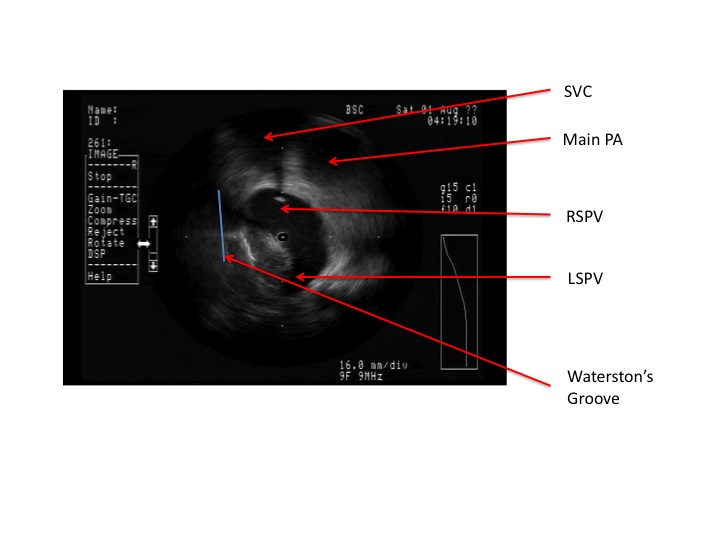

Isolation of the right pulmonary venous antrum begins with reorienting the ICE catheter by clockwise rotation of the steerable sheath around the posterior left atrium and into view of the right pulmonary veins as shown in picture below. This view typically looks like Edward Munch’s The Scream with the SVC and main PA representing the eyes and the right pulmonary venous antrum the mouth.

With the ICE catheter in position at the right pulmonary venous antrum, we can then begin a primary encircling lesion of this antrum. Once the entire antrum is encircled by the primary line, the right superior (RSPV) and right inferior (RIPV) are then evaluated for entrance and exit block. The next video shows the ICE catheter entering the RSPV. Towards the end of the video you can see the ablation catheter directed into the superior aspect of the RSPV. Of note, in this view one can see how Bachman’s bundle can come across the septum and run over the RSPV on its way to the LSPV. Additionally, the phrenic nerve often runs near the septal aspect of the RSPV at 9 o’clock so pacing in this area is mandatory prior to ablation to avoid diaphragmatic paralysis.